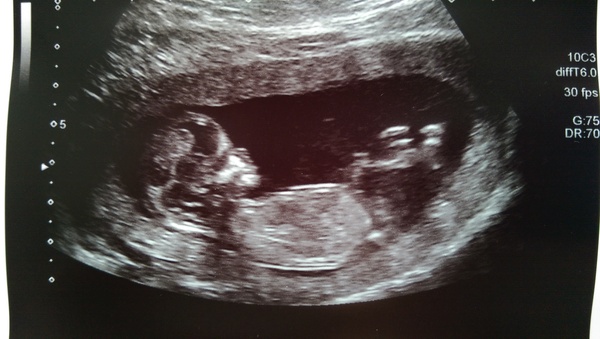

clara we also had a sleepy baby. A couple of jumps, then hand on its face, then it turned over and started cuddling it's placenta. Cute thing. All is good! We didn't have the downs screening but she said the nuchal looked normal. 13+2, due date 6th Feb. They took such good care of us as well - I've got two more scans booked in before the 20 weeks in September just to check all is well. I'm currently in love with the NHS and my consultant is definitely getting a card and a massive bunch of flowers at the end of this!

haquoi123 · 03/08/2015 12:21

Ah poo, forgot to add pic!

Yay haqoi fantastic :) great little scan pic. I've been impressed with the NHS so far too although my care has been very routine so far.

Wow haqoui that is a really clear pic. You must have been bursting for a wee! The sonographer told me my bladder wasn't very full. As she was squashing me with the scanner I begged to differ but she said 'even a small amount of urine feels like your bladder's full when you're pregnant'.

Fab pic Haquoi and so weird about the nosebleeds Confused Such strange things our bodies are!

haquoi lovely pic